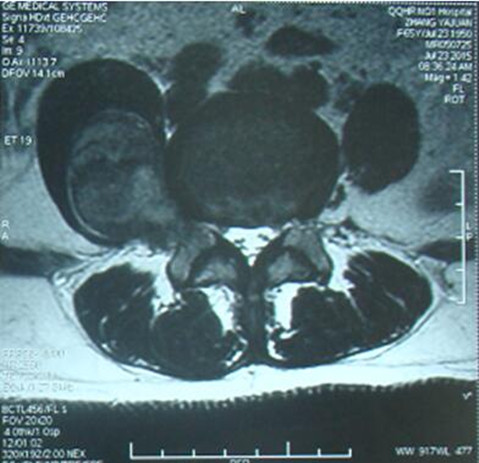

赵先生45岁,于2015年7月发现左侧腹部有一无痛性肿物,约鸡蛋大小,赵先生认为这肿物不痛不痒,就没重视。可随着时间推移,肿物逐渐增大,李先生出现左下肢疼痛、麻木的症状,包块增长至约拳头大小,疼痛明显加重,甚至无法入睡,严重影响李先生生活质量,仅半年时间,体重减轻10kg,在外院行增强CT检查示:“左侧腹膜后占位,考虑间叶源性肿瘤可能性大”。为求进一步诊治,李先生多方打听来我院骨外一科就诊。确诊后,白玉江主任决定为此其行肿物切除术。术中见腹外斜肌下方肿物,手术难度及风险极大,经过两个小时的手术,最终将15×10×10cm3巨大肿瘤完整切除。术后病理回报:粘液性脂肪肉瘤。术后一个月及两个月随访,患者左下肢疼痛无复发。

手术难度:由于患者有肿瘤病史,且此重物巨大在盆腔内,无活动度,手术难度极大,因肿物巨大与周围组织粘连,手术时间较长,并极有可能造成输尿管、腹膜、肠管、神经的损伤;该肿瘤恶性可能性大,若侵犯周围组织,需扩大切除;其中最危险的是肿物在盆腔与左髂骨粘连且无活动度,若将其完整切除极有可能损伤盆底静脉丛,造成大量失血,引起失血性休克导致患者死亡。

入院后腹部MRI